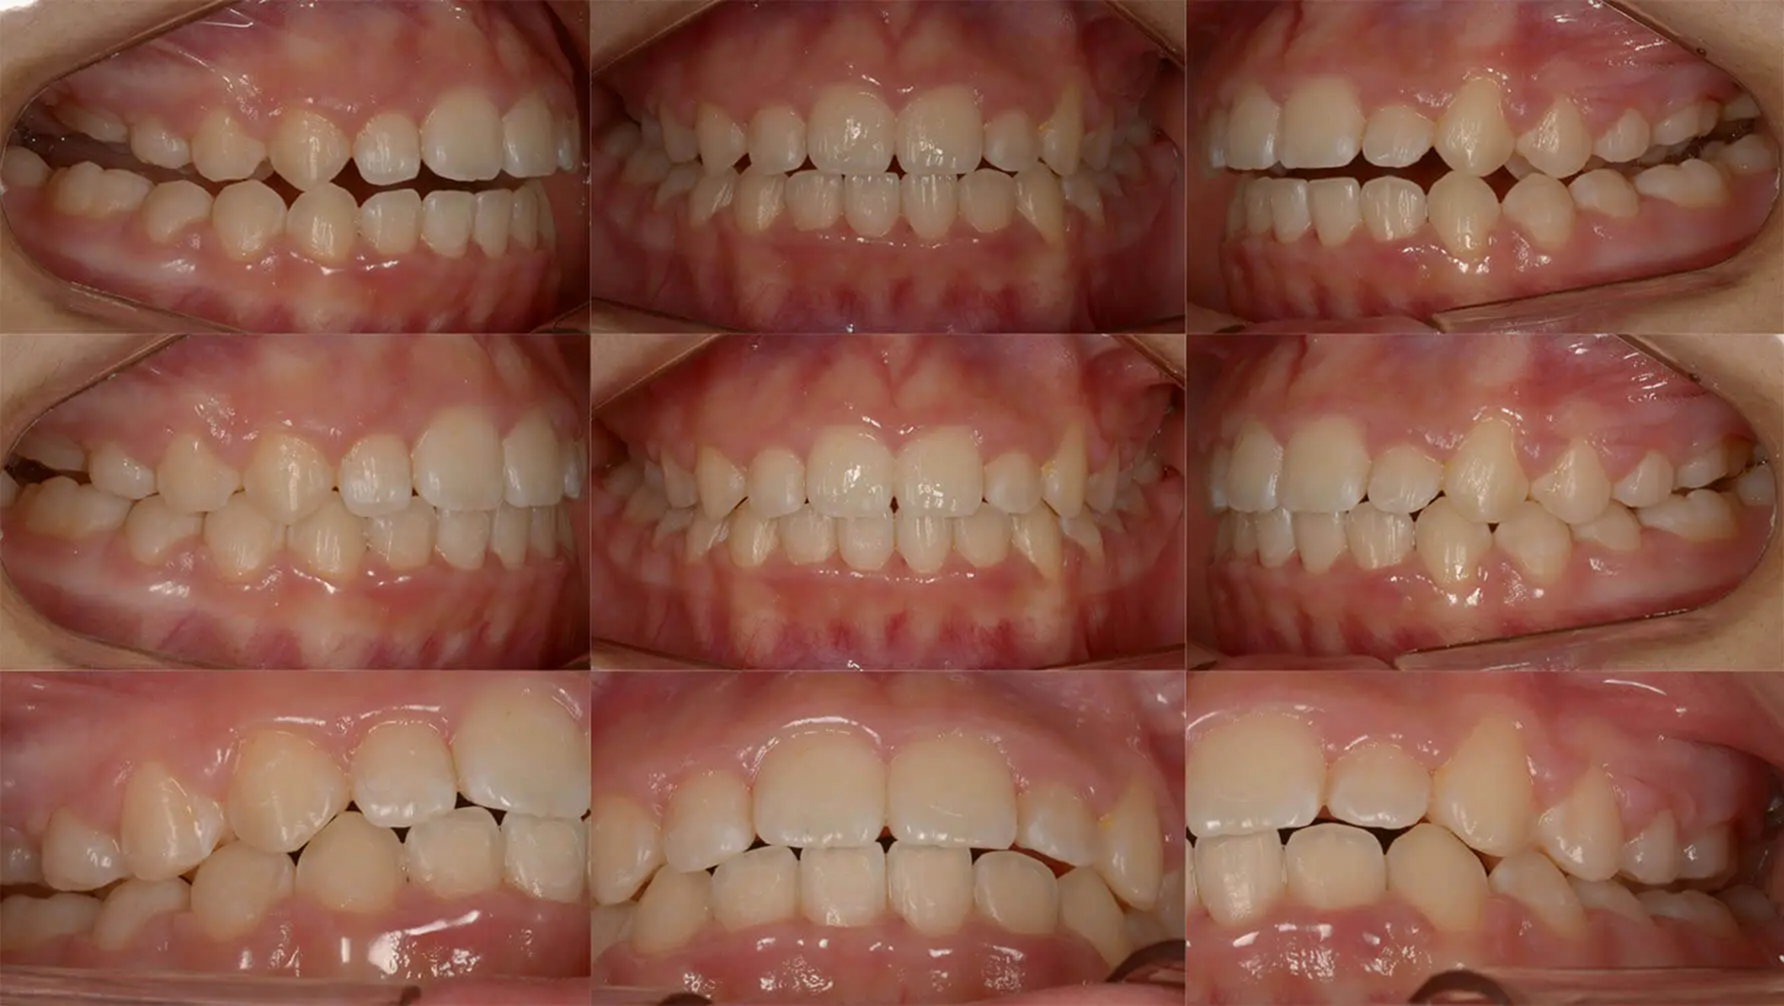

Case02凸凹とを歯を抜かずに改善した症例

全体的な歯列不正が著しく、ブラッシングがしにくい状態でした。永久歯の異所萌出により両側上顎乳犬歯は晩期残存していました。診査の結果、歯列の狭窄を認めたため、オーバーレイアーチによる拡大を行えば、抜歯なしで矯正できると診断しました。かなり窮屈な部位もありましたが、きれいに歯列を整えました。むし歯治療も適正に行い、審美的な状態を獲得しました。

初診 2017.5.16

矯正治療開始 2017.8.7

ファイナル 2018.11.13

| 主訴 | 全体的な凸凹をきれいにしたい |

| 診断 | 両側アングル1級の叢生 |

| 矯正方法 | オーバーレイアーチを用いたマルチブラケット |

| 矯正期間 | 13か月・15回 |

| 費用 | 710,000円(税別) |

| 調整料 | 月1回 5,000円(税別) |